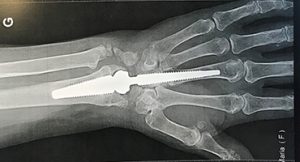

Examens d’imagerie

Les examens d’imagerie sont réservés aux situations ambiguës ou résistantes au traitement :

• Échographie : montre un épaississement de la gaine tendineuse, un épanchement et parfois un frottement tendineux. C’est l’examen le plus utile et non invasif.

• IRM (rare) : utilisée lorsque l’échographie n’est pas concluante ou dans des formes atypiques, permettant de visualiser précisément l’inflammation et d’exclure une atteinte osseuse ou articulaire.

Ces examens confirment la présence d’une inflammation du premier compartiment dorsal et permettent d’exclure d’autres causes de douleur du pouce ou du poignet.